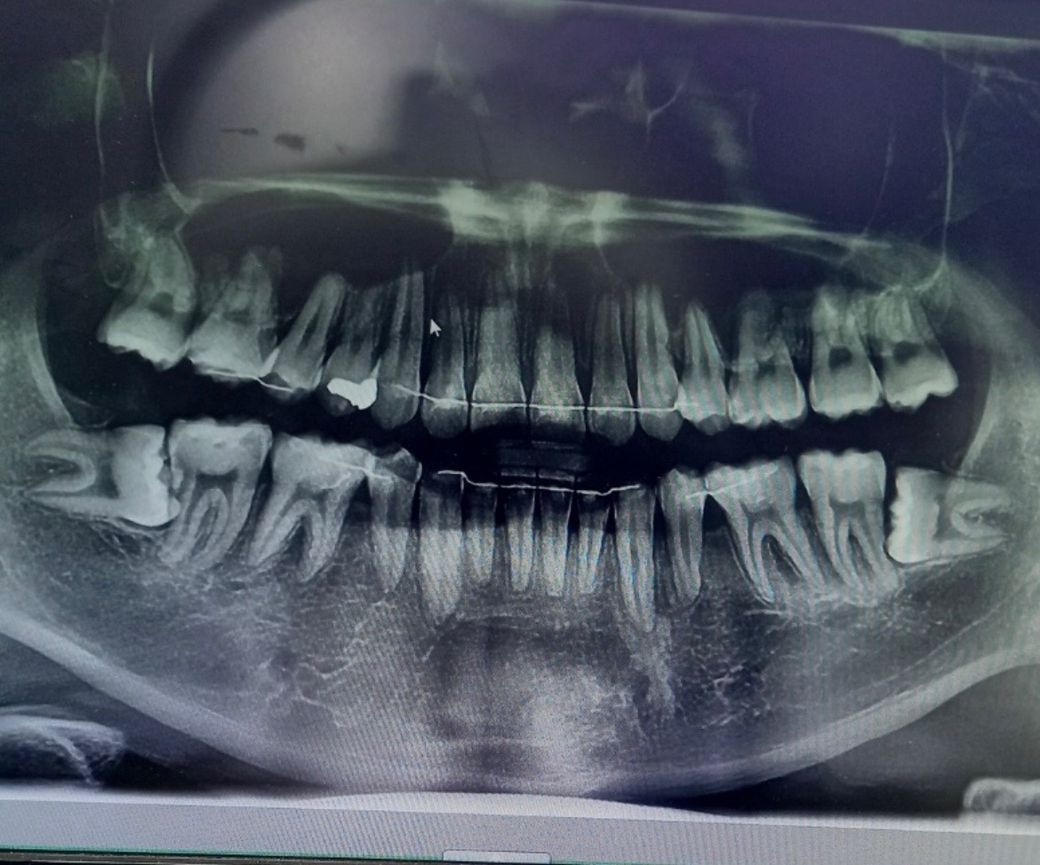

제가 사랑니 발치 2년정도 방치했는데..

제가 곧 군 입대를 해서 안 뽑고 있었는데 전역하고 갑자기 생각나서 애일 바로 뽑으러 갈려고 합니다 2년 전에도 이정도 였는데 지금은 많이 심각해졌을 가능성 있을까요..?

사랑니 자체는 더 상황이 나빠지거나 그럴 건 없습니다. 다만, 그 옆 어금니에 옆구리부위 충치가 생겼을 순 있습니다.

기울어져 있는 사랑니로 인해서 오른쪽에 있는 치아에는 인접면 충치가 생겼을수 있습니다.

이런경우 발치를하고 충치를 치료하는것이 좋습니다.